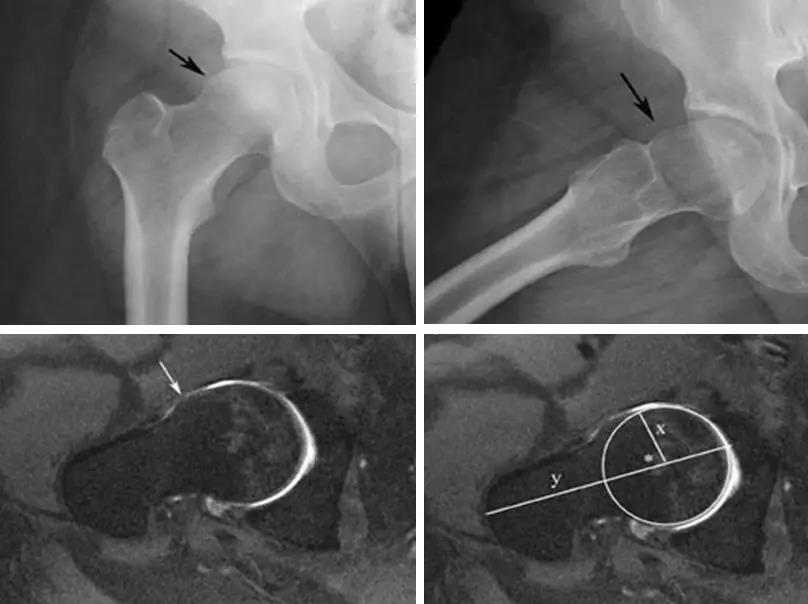

凸轮撞击型FAI▼

- 股骨头颈间的凹陷不足,伴局部的骨质增生。

- 股骨头颈的“ 枪柄样” 畸形。

- 股骨头颈联合处前上缘骨性突起。

- 非圆形的股骨头。

- 股骨头颈联合处前缘骨性突起、骨质硬化,α角增大。